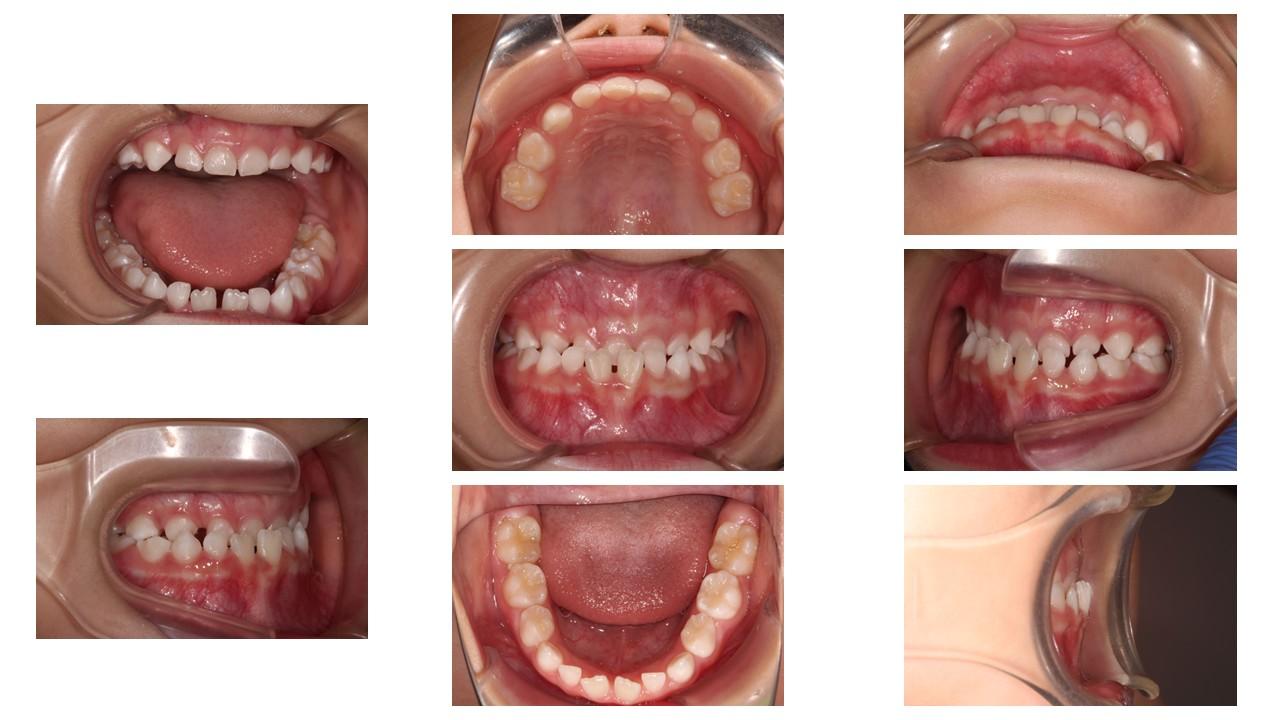

「叢生」は、一般的に「乱ぐい歯(らんぐいば)」「八重歯(やえば)」「ガタガタの歯並び」などと呼ばれる状態で、日本人に非常によく見られる不正咬合(ふせいこうごう:良くない噛み合わせ)です。

<叢生の状態>

顎(あご)の骨の大きさに対して、歯のサイズが大きすぎたり、歯が並ぶスペースが不足していたりするために、歯がデコボコに重なり合って生えている状態を指します。

【叢生を治す必要がある理由】

叢生は見た目の問題だけでなく、お口の中の健康を維持することを難しくし、将来的に様々なトラブルを引き起こす原因となります。